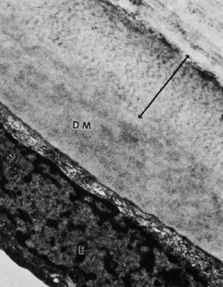

normal cornea. Arch Ophthalmol 100:1942, 1982 87. Bourne WM, Johnson DH, Campbell RJ: The ultrastructure of Descemet's membrane. III. Fuchs' dystrophy. Arch Ophthalmol 100:1952, 1982 88. Binder PS, Rock ME, Coalwell Schmidt K, et al: High-voltage electron microscopy of normal human cornea. Invest Ophthalmol Vis Sci 32:2234, 1991 89. Tamura Y, Konomi H, Sawada H, et al: Tissue distribution of type VIII collagen in human adult and fetal eyes. Invest Ophthalmol Vis Sci 32:2636, 1991 90. Klyce SD, Beuerman RW: Structure and function of the cornea. In Kaufman HE, Barron BA, McDonald MB, Waltman SR (eds): The Cornea. New York: Churchill Livingstone, 1988:3–54. 91. Williams K, Watsky M: Gap junctional communication in the human corneal endothelium and epithelium. Curr Eye Res 25:29, 2002 92. Waring GO, Bourne WM, Edelhauser HF, et al: The corneal endothelium: Normal and pathological structure and function. Ophthalmology 89:531, 1982 93. Kreutziger GO: Lateral membrane morphology and gap junction structure in rabbit corneal